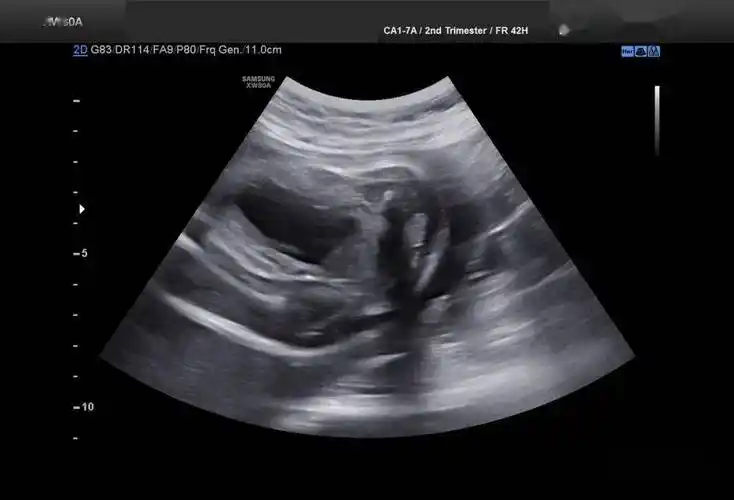

诊断胎儿尿道下裂前请先搞清男女!_膀胱_郁金香_男孩子